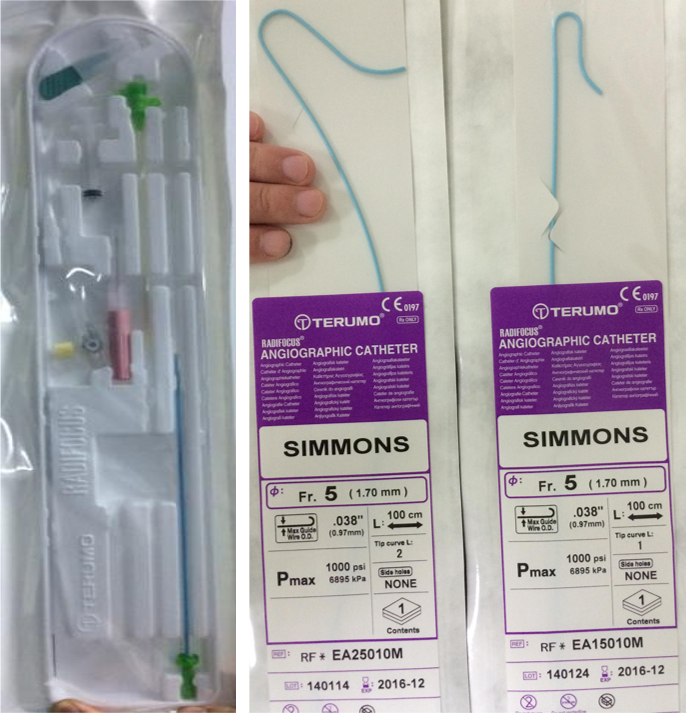

1.桡动脉鞘管

3.Simmons导管:5F,1m,型号Sim1、2、3。Sim2更适合国人。